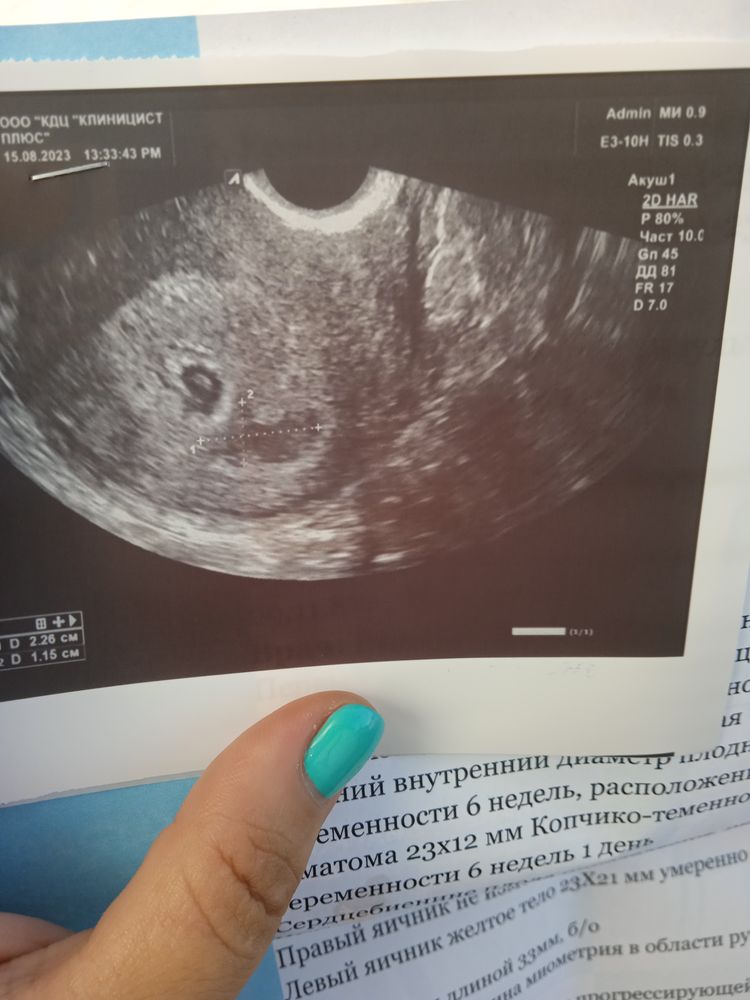

Кто с гематомой выносил? Что делали. К гинекологу завтра экстренно поеду.

Гематомы бывают больше чем у 50% беременных.У меня в 6 недель тоже была.Половой покой,тяжести не поднимать и не стрессовать.